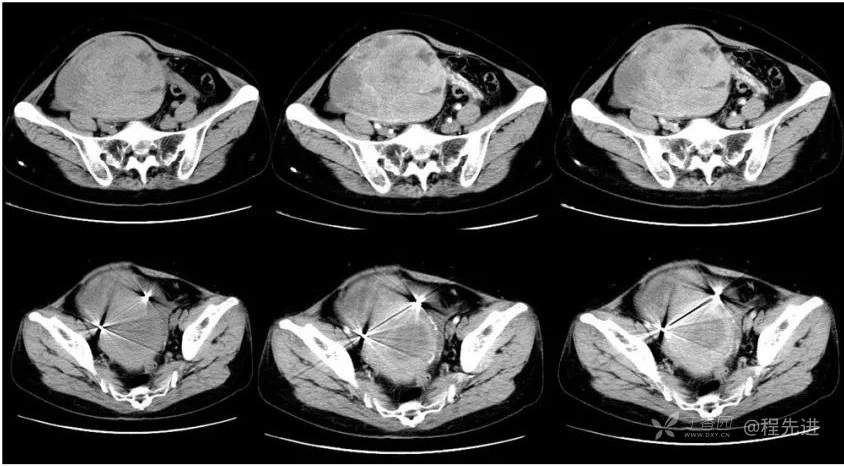

B超:中腹部混合回声肿块,性质待定